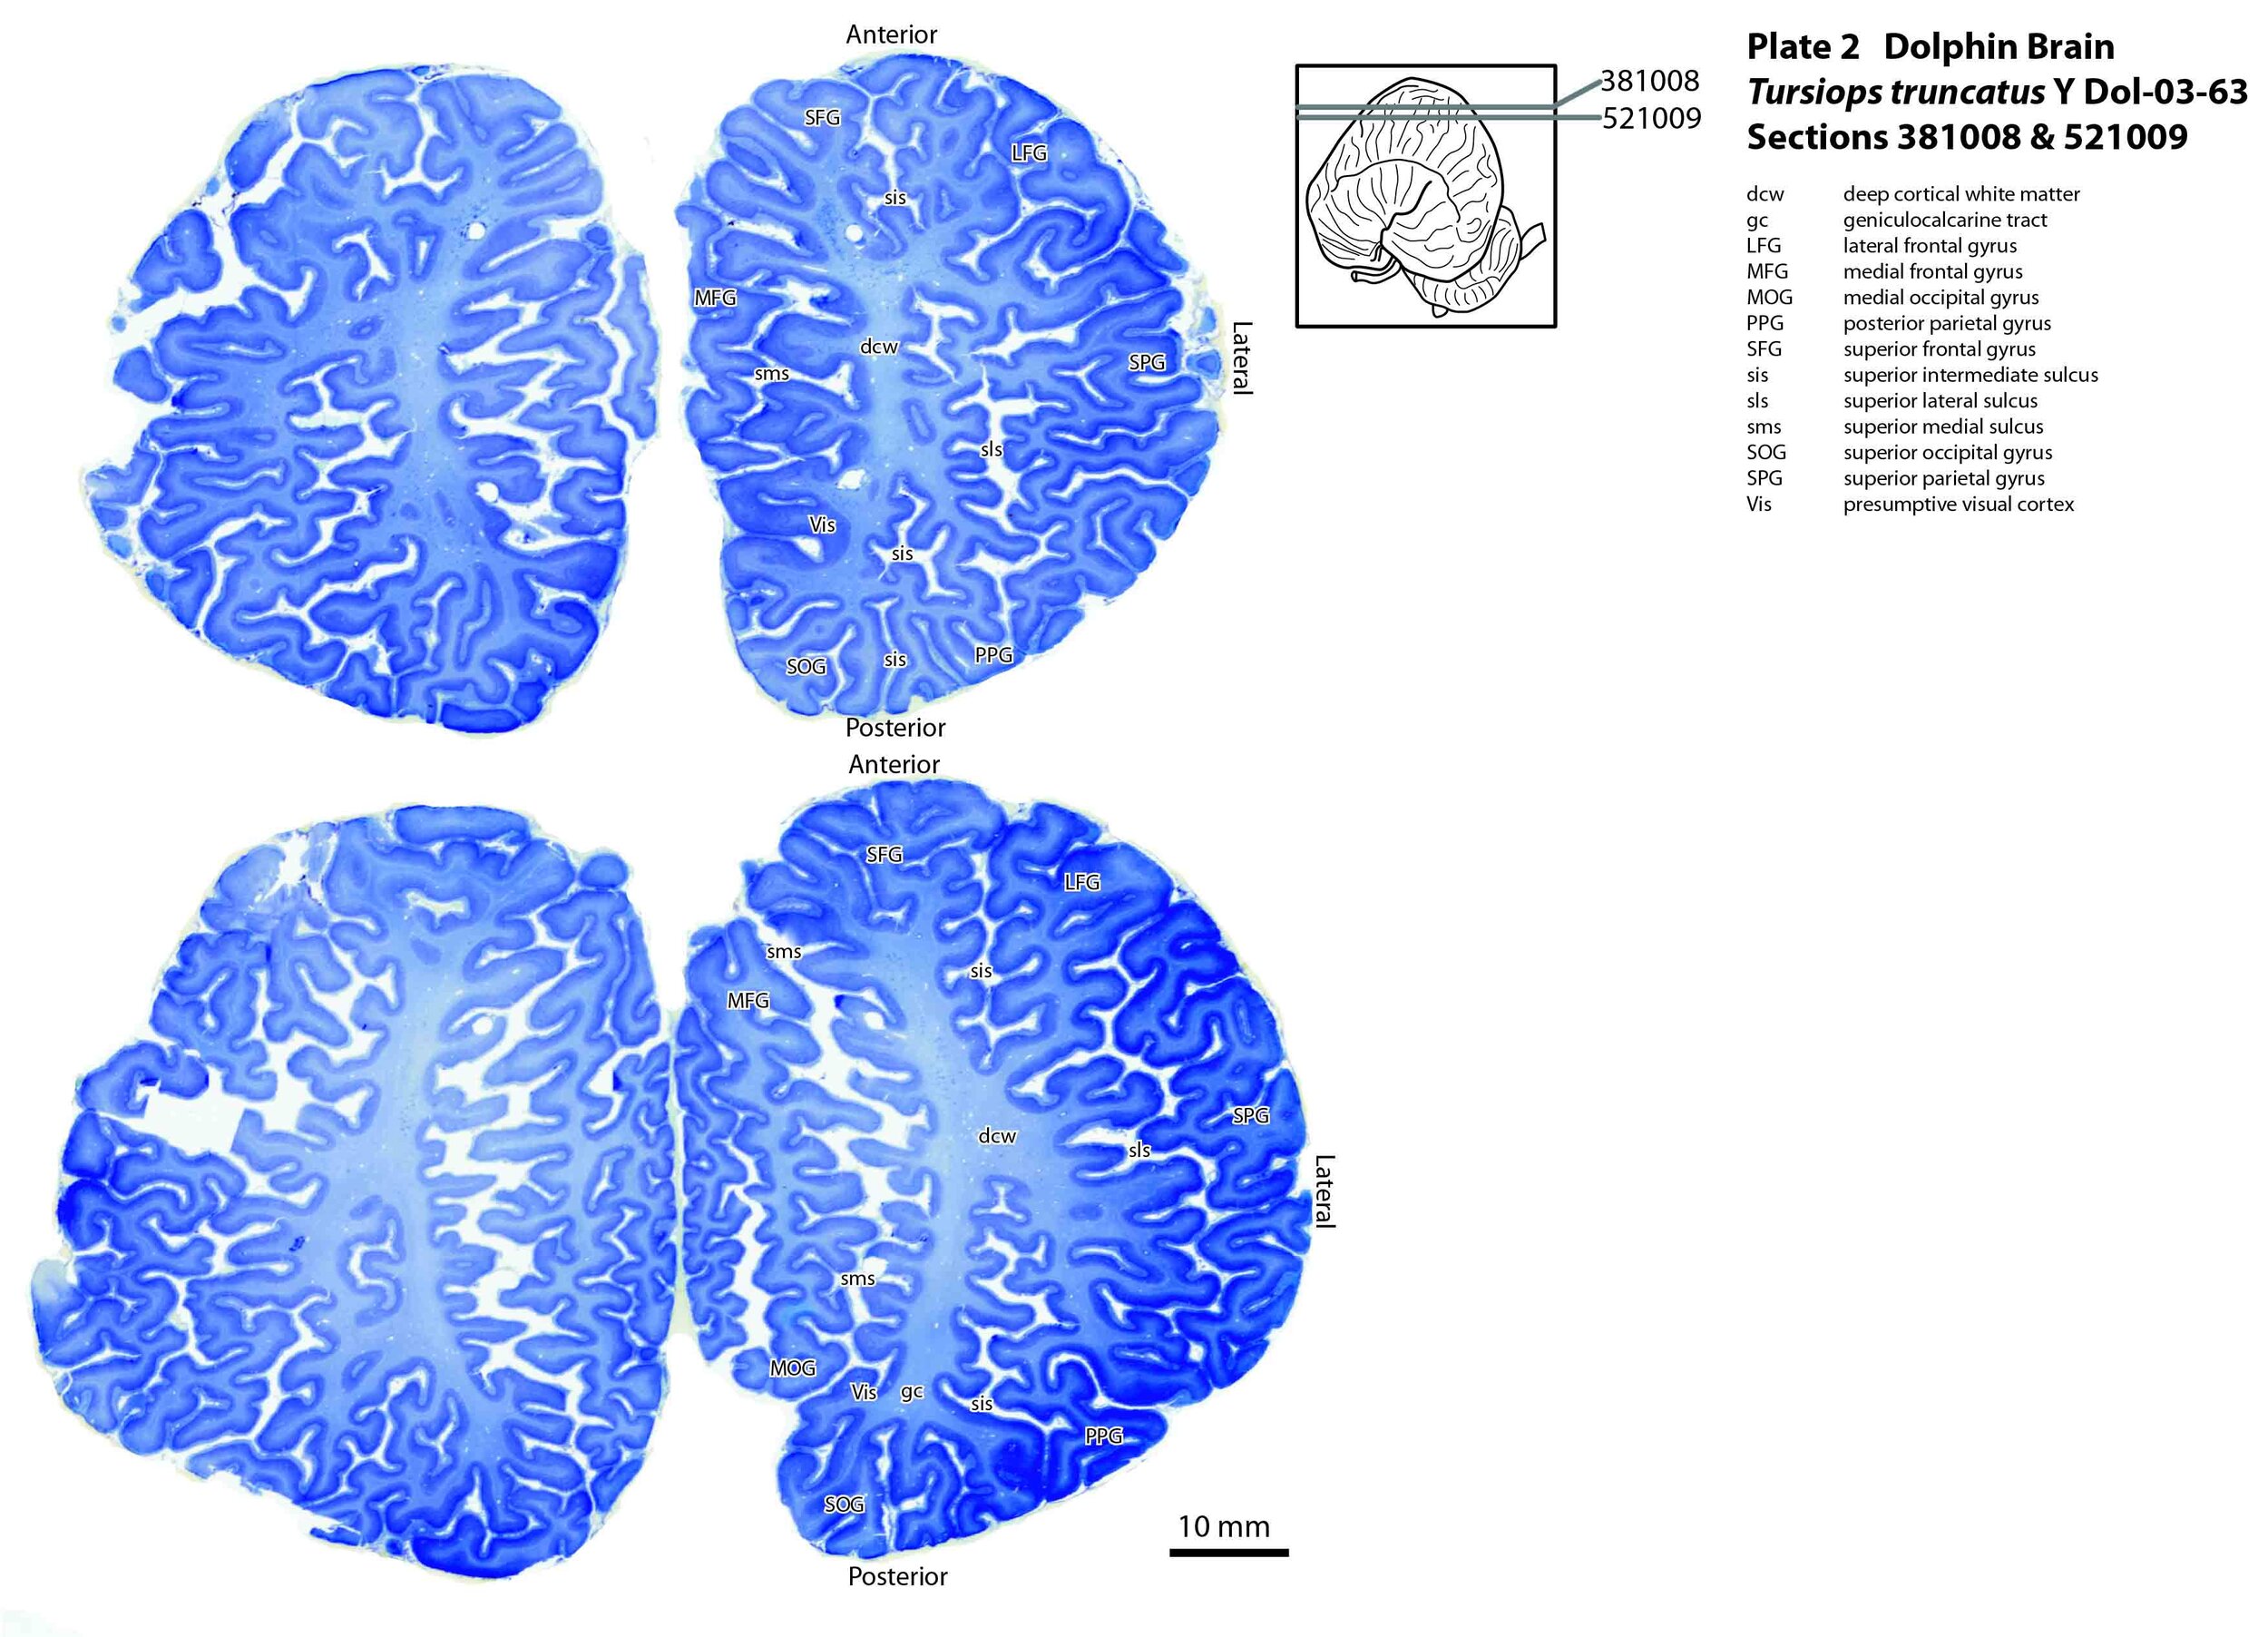

Cetacea

Representative: Dolphin • Present Day

Dolphin brain showing extreme gyrencephalic folding

Dolphin Brain: Extreme Folding (Hyper-Gyrencephalic)

FOLDING LEVEL: 85% - Extremely Dense Folding

Movement Complexity Profile

• Six Degrees of Freedom: Movement and rotation on all three axes in 3D fluid environment

• Echolocation: Real-time sound emission, echo processing, and spatial navigation

• Hydrodynamics: Precise control of flukes and flippers for graceful maneuvering

Brain Structure

• One of the most convoluted brains in nature

• Surface area rivals and sometimes exceeds humans

• Extreme gyrification for 3D navigation

Folding-Movement Justification: The dolphin's extreme cortical folding (85% surface area increase) represents the pinnacle of movement-brain co-evolution. The hyper-dense folding provides the massive computational power needed for 6-degrees-of-freedom movement in a 3D fluid environment. Each fold processes the incredibly complex proprioceptive data from echolocation-guided navigation, where the entire body becomes both a sound transmitter and receiver. The myofascial system must coordinate precise fluke movements for hydrodynamic efficiency while the brain simultaneously processes acoustic spatial maps. This represents the most complex "language of motion" in nature, requiring the most extensively folded brain architecture.